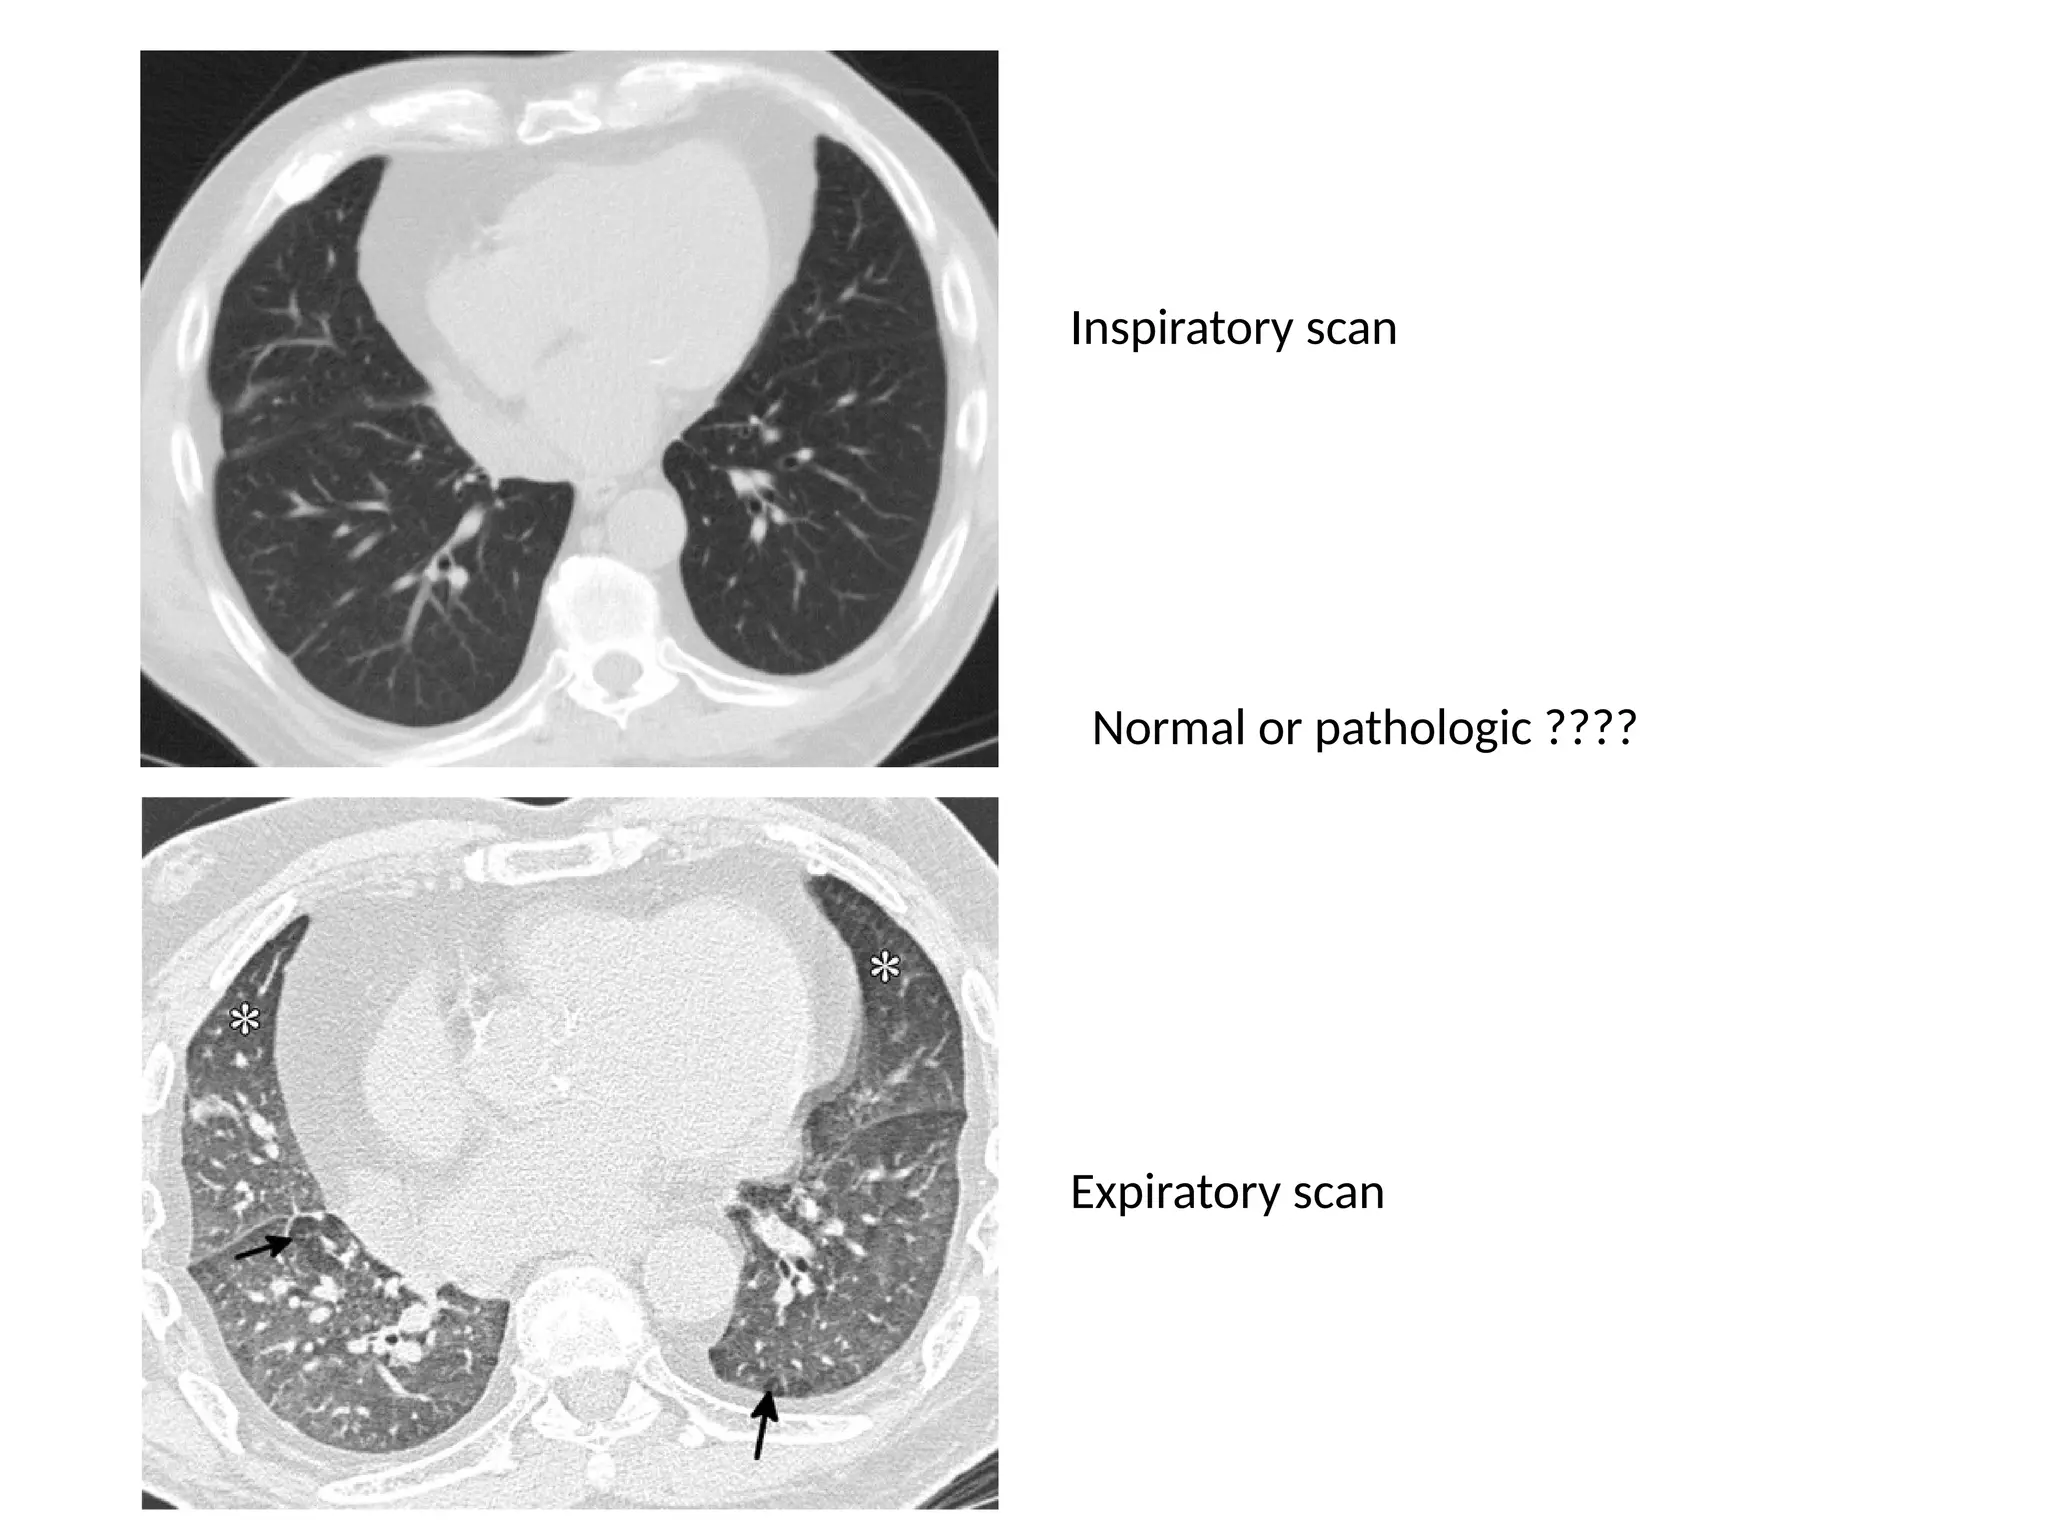

Inspiratory scan

Expiratory scan

Normal or pathologic ????

Small airway disease or chronic thromboembolism???

How to differentiate??? •There are two diagnostic hints for further differentiation: • Look at expiratory scans for air trapping • Look at the vessels • If the vessels are difficult to see in the 'black' lung as compared to the 'white' lung, than it is likely that the 'black' lung is abnormal. Then there are two possibilities: obstructive bronchiolitis or chronic pulmonary embolism. Sometimes these can be differentiated with an expiratory scan. If the vessels are the same in the 'black' lung and 'white' lung, then you are looking at a patient with infiltrative lung disease, like the one on the right with the pulmonary hemorrhage.